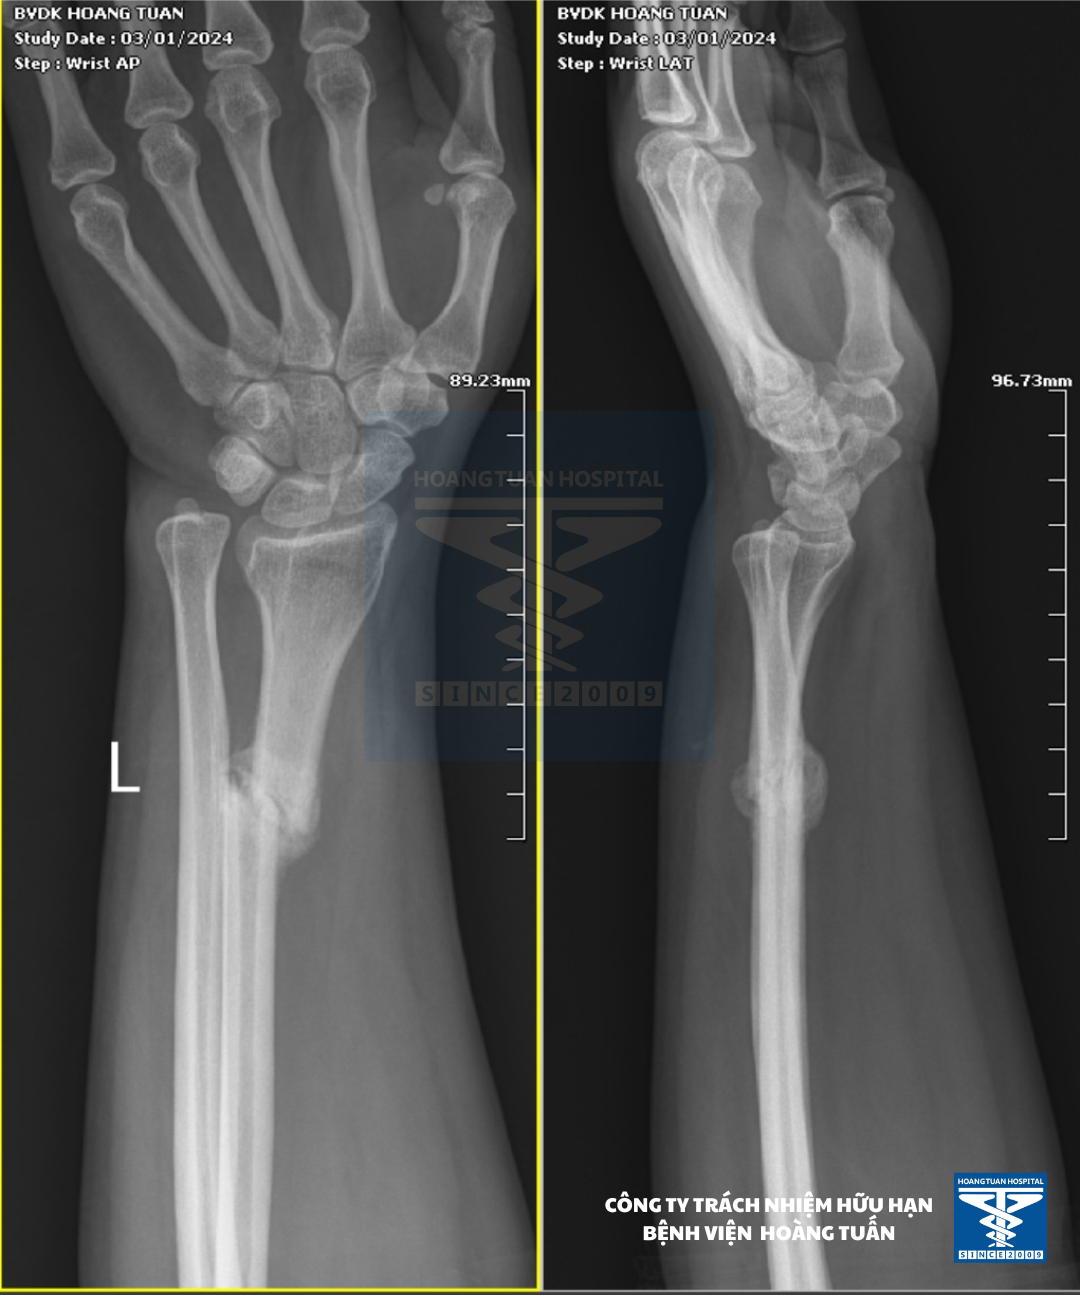

Vừa qua, vào Tháng 1 năm 2024 Bệnh viện Đa khoa Hoàng Tuấn tiếp nhận một bệnh nhân nữ 41 tuổi tự té chống vùng tay trái trực tiếp xuống đất, gãy xương vùng cẳng tay trái điều trị bó bột và đắp thuốc bắc trong 5 tuần không bớt. Đến với Bệnh viện đa khoa Hoàng Tuấn bệnh nhân được chỉ định chụp X-quang cẳng bàn tay trái, kết quả ghi nhận gãy 1/3 dưới xương quay bên trái kèm trật khớp quay trụ dưới (kiểu gãy Galeazzi). Đây là trường hợp gãy cũ “Galeazzi” và được các bác sĩ Chuyên khoa Chấn thương hội chẩn chỉ định phẫu thuật nắn trật cố định kèm kết hợp xương quay bên trái.

Hình 1. Hình ảnh xương cẳng tay (T) của bệnh nhân trước mổ